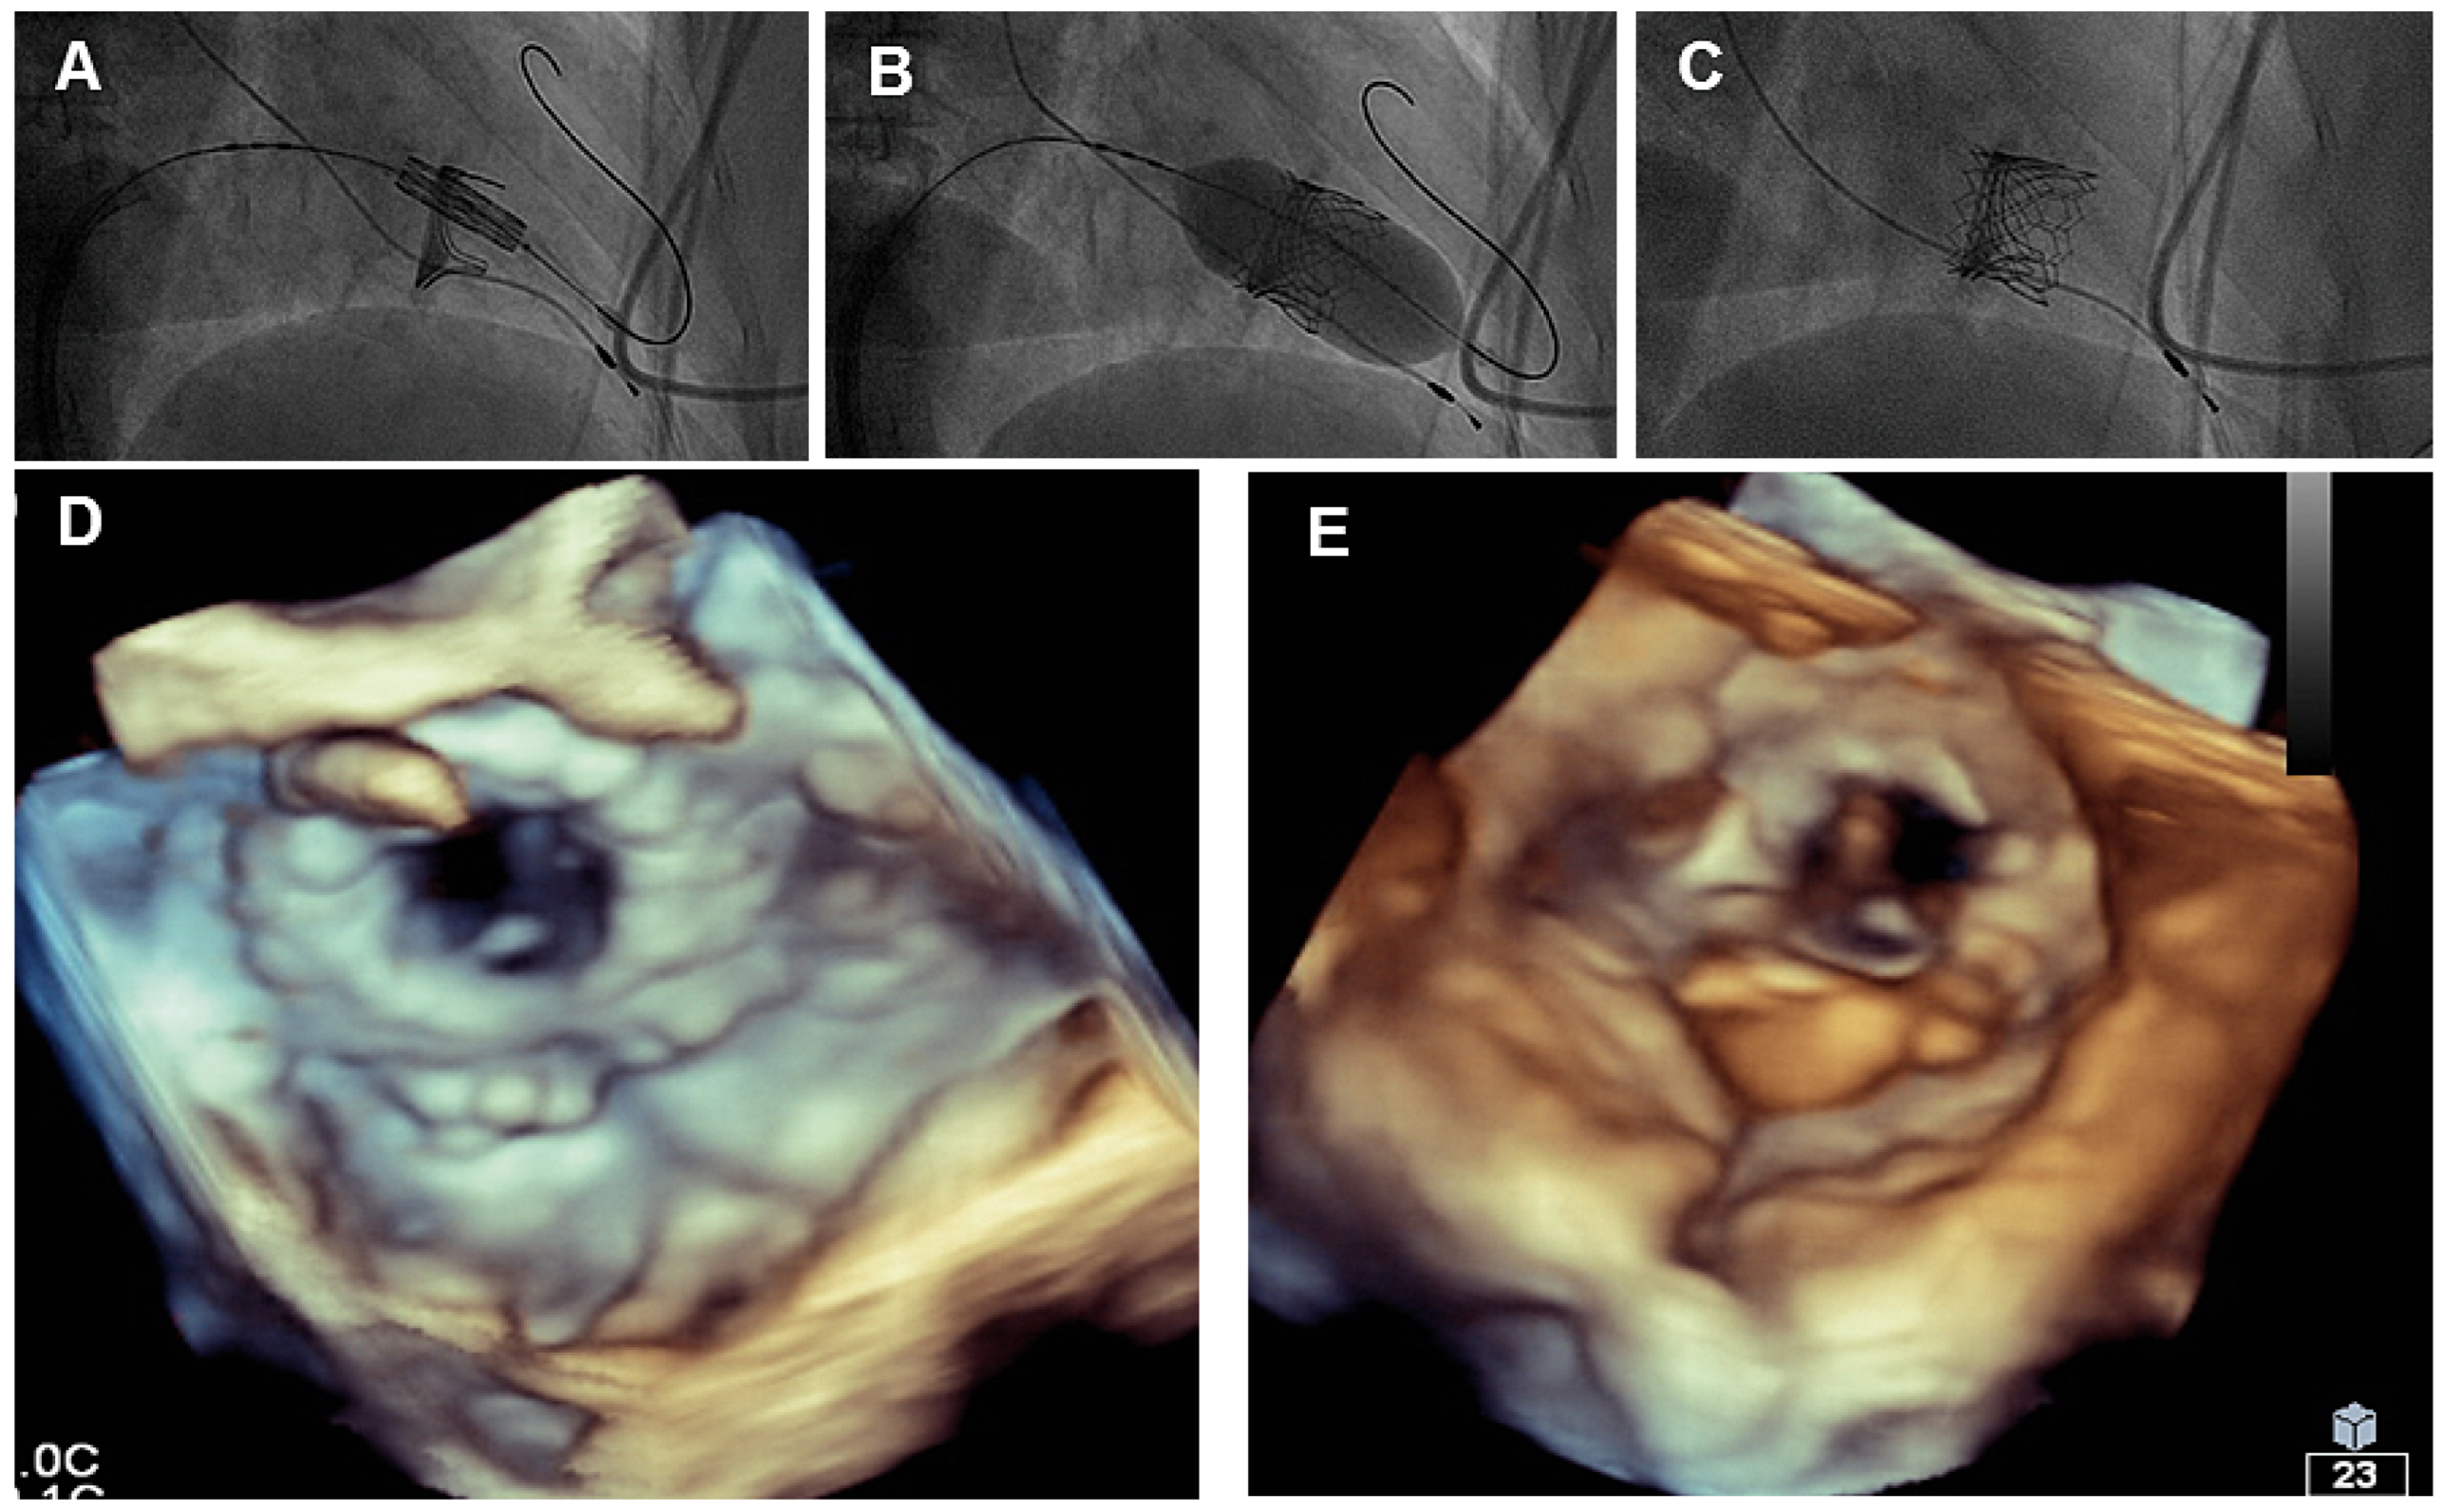

Cardioband at the tricuspid position